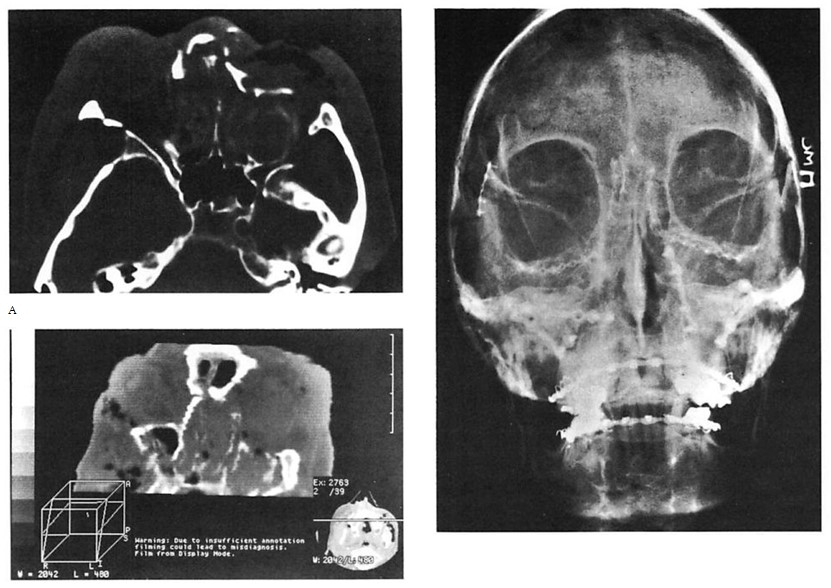

Fig 8. Comminuted nasoethmoid orbital and Le Fort fractures managed in a multiply injured 82-year-old woman. (No internal orbit reconstruction was performed.) (A) Preoperative axial computed tomographic (CT) scan. (B) Preoperative coronal reconstruction shows displacement of medial orbital walls. (Cervical-spine injuries precluded positioning for coronal scan.) (C) Postoperative coronal view (reconstructed) at 4 weeks shoivs stable reduction of medial orbital walls. (D) Postoperative plain film shows fixation used. (E) Clinical result 6 months postoperatively.

Fig 8. Comminuted nasoethmoid orbital and Le Fort fractures managed in a multiply injured 82-year-old woman. (No internal orbit reconstruction was performed.) (A) Preoperative axial computed tomographic (CT) scan. (B) Preoperative coronal reconstruction shows displacement of medial orbital walls. (Cervical-spine injuries precluded positioning for coronal scan.) (C) Postoperative coronal view (reconstructed) at 4 weeks shoivs stable reduction of medial orbital walls. (D) Postoperative plain film shows fixation used. (E) Clinical result 6 months postoperatively.

Fig 9. Computed tomographic (CT) scans of patient who suffered low-energy Le Fort II and III fractures treated with miniplates at the Le Fort I level and microplates along the infraorbital rims. (A) Preoperative CT shows pronounced impaction of central midface. (B) Axial scan through infraorbital rim shows anatomical reduction 3 days postoperatively. (C) CT scan at I year at similar cut shows unchanged position of bone fragments after healing.